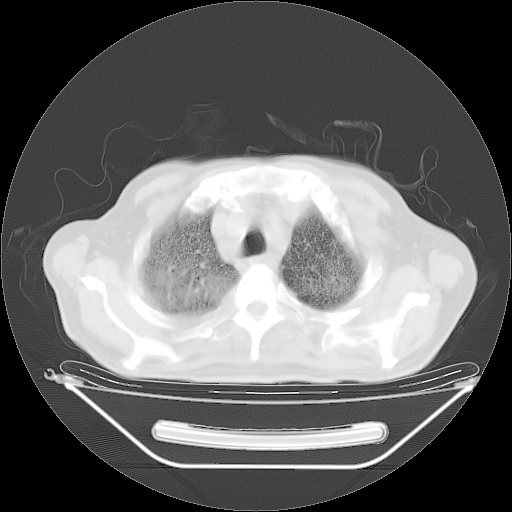

今天复查肺部CT,发现双肺广泛磨玻璃样改变。所以我把3月19日和5月9日相隔50天的肺部CT上传。请大家会诊。

2009年3月19日肺部CT片。

5月9日肺部CT(在4月27日齐鲁医院肺部CT描述部分肺组织磨玻璃样改变,12天后肺组织广泛磨玻璃样改变)